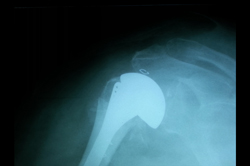

Shoulder Replacement